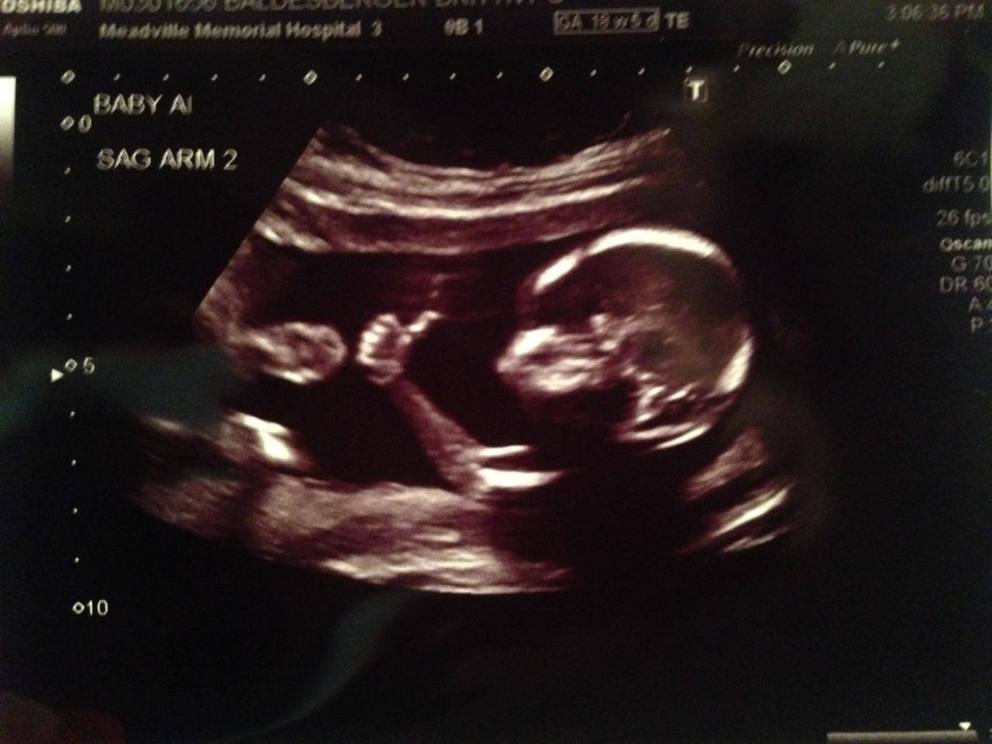

Ma poi, davanti alla fotografia di un figlio che dal grembo materno quasi saluta facendo “Ok” – com’è accaduto in questi giorni ad una coppia della Pennsylvania e come già accadde nel 2011 ad una madre di Manchester – il nostro corposo elenco di parole si rivelerebbe subito per quello che è: un cumulo di menzogne, un vergognoso tentativo di rendere l’aborto procurato – a sua volta mascherato come «interruzione volontaria di gravidanza», come se una guerra che uccide innocenti si potesse definire «interruzione improvvisa di esistenze» – meno grave e la nostra coscienza più pulita. Per tutte le volte che, per non riconoscere la meravigliosa realtà di un figlio o di un fratellino, abbiamo cambiato discorso o, più crudelmente, abbiamo scelto di mentire.